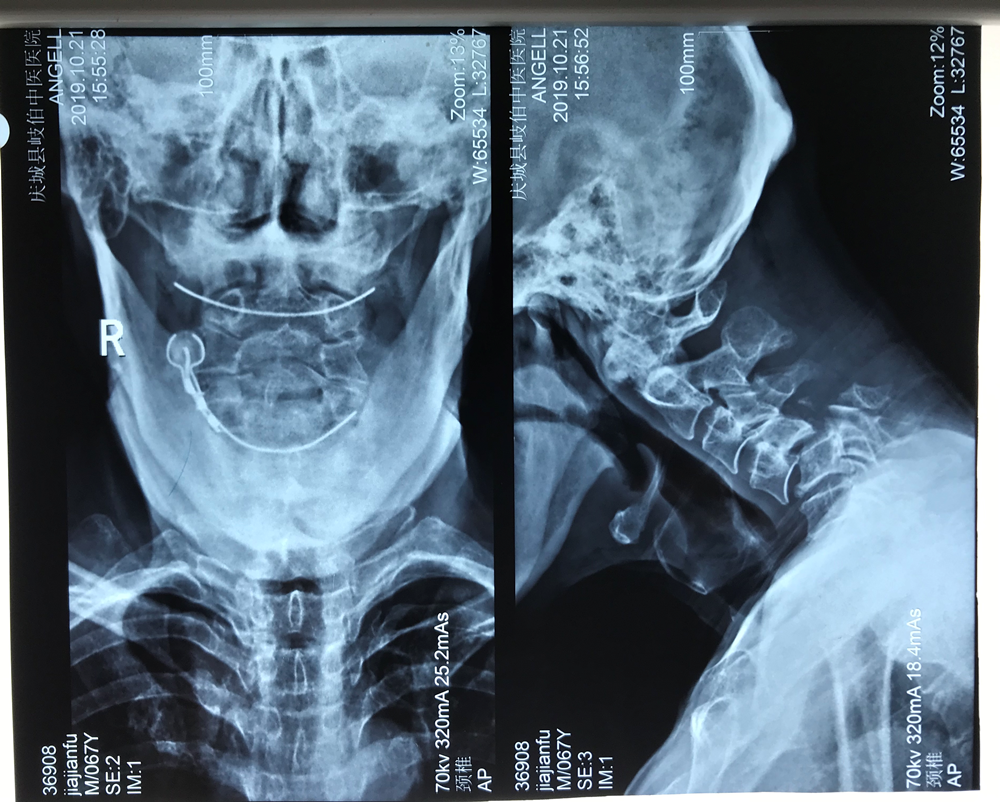

患者67岁,男性,在家劳作时不慎从高处摔下,头部落地,致颈部受伤,受伤当时即感觉颈部疼痛并有双上肢麻木、活动受限,被家属紧急送往当地医院就诊,相关检查后明确诊断:颈4椎体完全性滑脱并颈5椎体骨折。因手术难度高,患者随即转诊至我院骨一科就诊。科室迅速组建救治团队,经过缜密的术前讨论,决定首先行颅骨牵引手术,缓解患者神经受压症状,随后根据患者情况细化手术方案——决定全麻下为患者一期行颈椎前后联合入路切开减压、脊髓探查、椎体滑脱复位内固定手术治疗。